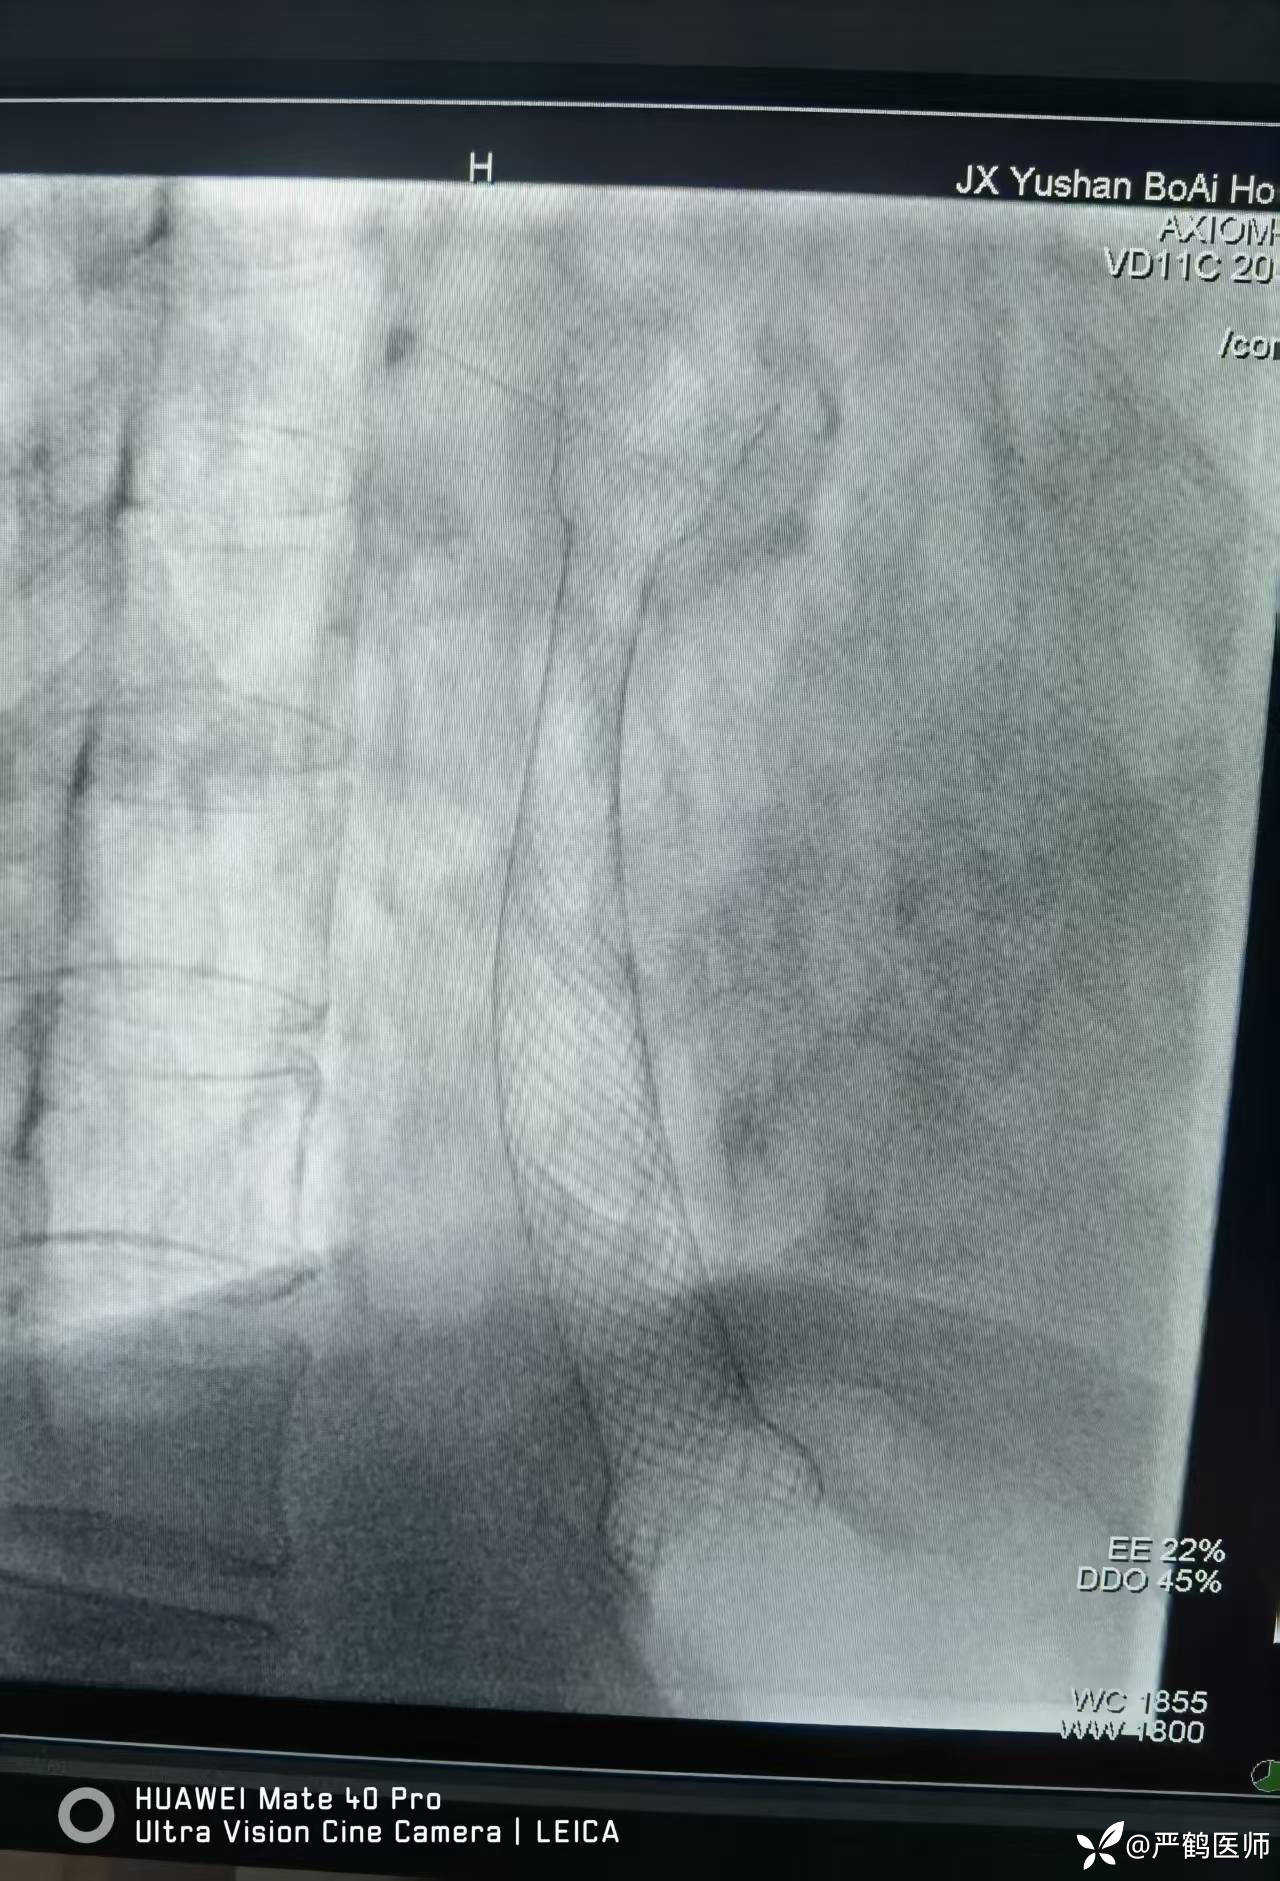

食管癌覆膜支架置入术

老年男性,食管距门齿30cm处肿瘤至进食梗阻,无法手术,家属不愿进一步行放化疗治疗,置入全覆膜食管支架解除梗阻,缓解进食困难症状